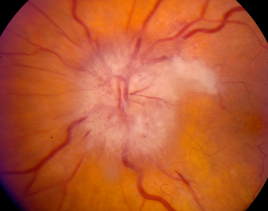

Ocular manifestations are common in GCA and can arise at any time, including during treatment. The most common ocular manifestation of GCA is visual loss, most often secondary to arteritic anterior ischemic optic neuropathy (AAION).[35] In these cases, the short posterior ciliary arteries are occluded by intimal hyperplasia secondary to systemic inflammation.[35][36][37][38][39] Once occluded, the short posterior ciliary arteries cannot provide blood to the prelaminar and laminar portions of the optic nerve head, which results in an ischemic injury to the anterior portion of the optic nerve (AAION). Pallid optic nerve edema is a common finding.

A similar phenomenon, which is classically not associated with GCA, is non-arteritic ischemic optic neuropathy (NAION). NAION is due to hypoperfusion of the terminal para-optic branches of the short posterior ciliary artery, leading to optic disc ischemia. This condition presents with either segmental or diffuse optic nerve head edema with hemorrhage, which can evolve to pallor. However, there have been reported cases of biopsy-confirmed AAION secondary to GCA presenting with segmental disk edema without pallor, mimicking NAION. These cases were presumed to be due to GCA involving only a subset of the short posterior ciliary arteries supplying the optic nerve head. Therefore, it is important to have a high index of suspicion for GCA when examining patients with atypical presentation of NAION.

Arteritic anterior ischemic optic neuropathy is characterized by acute monocular vision loss accompanied by optic disc edema. The optic disc edema in AAION is usually diffusely “chalk white,” and may be accompanied by disc hemorrhage, retinal whitening, or cotton wool spots (Figure 3).[57] Adjacent retinal whitening and cotton wool spots are crucial findings that indicate concurrent retinal ischemia, and these should raise a clinician’s suspicion for GCA. Visual acuity is often 20/200 or worse, with up to 21% of patients with GCA demonstrating no light perception.[58] An obvious afferent pupillary defect is often present. Visual field loss in patients with AAION is typically in a central, arcuate, or altitudinal pattern.

As shown in Table 1, NAION is associated with small-crowded optic nerves, hypertension, diabetes, and hyperlipidemia,[31] whereas AAION is not necessarily associated with the same vascular risk factors. In addition, patients with GCA are typically older than those with NAION (i.e. 8th–9th decade vs. 6th–7th decade). In NAION, patients will usually not note any associated systemic symptoms such as headache, jaw claudication, scalp tenderness, weight loss, anorexia, fever, or myalgias/arthralgias. In general, the vision loss from GCA is more severe than with NAION, with one third of patients with AAION demonstrating a visual acuity worse than 20/200; most patients with NAION retain a visual acuity near 20/80.[118] Patients with AAION may complain of preceding amaurosis fugax as well as other ocular symptoms including diplopia, fellow eye involvement, or ophthalmoplegia.

The physical examination also differs between these two diseases. Whereas AAION is associated with a diffuse “chalky” white edema, eventual cupping of the disc, and possible coexistent retinal ischemia, NAION often demonstrates segmental optic nerve edema with eventual sectoral or total flattening and pallor.[36][58] In addition, laboratory evaluations such as ESR and CRP are usually normal in patients with NAION.